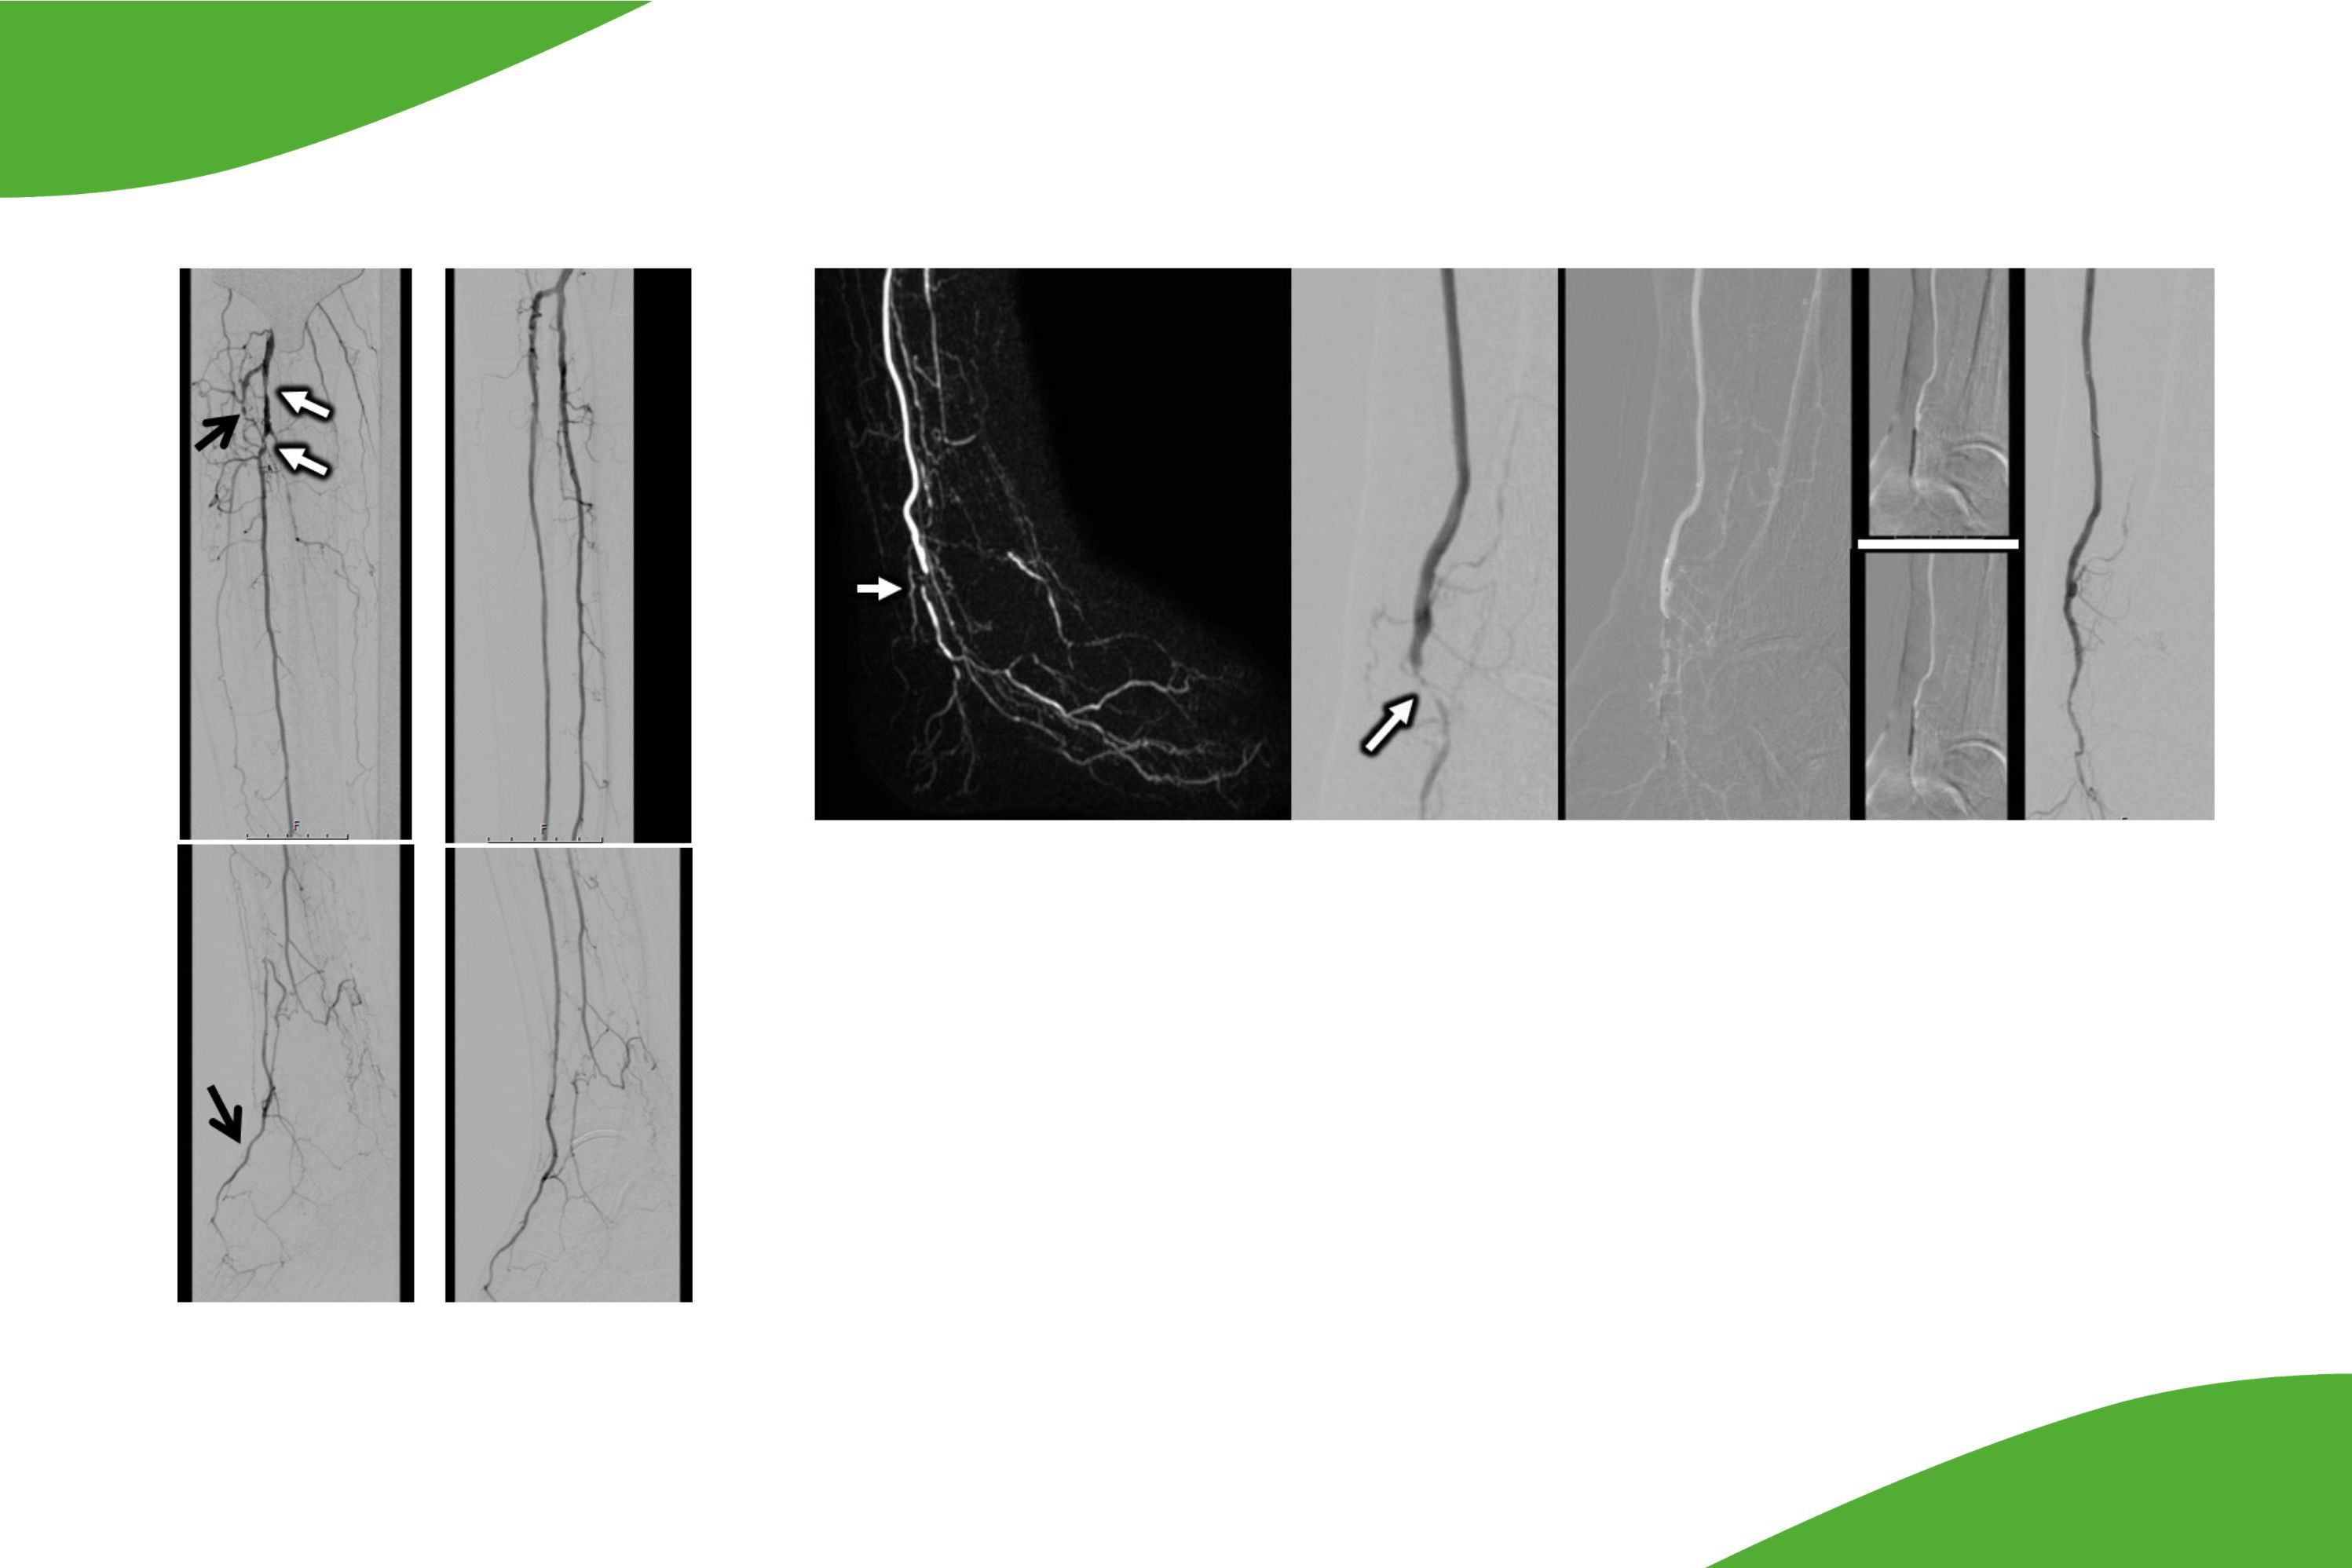

Durch Einsatz von sehr kleinlumigen Kathetersystemen ist heutzutage auch die Behandlung der kleineren Unterschenkelgefäße bis auf Höhe des Fußrückens möglich. Insbesondere bei Patienten mit drohender Fußamputation kann hier durch eine Rekanalisation der Unterschenkelgefäße eine verbesserte Durchblutungssituation erreicht werden, um eine Fußamputation möglichst zu vermeiden. Für eine solche Behandlung sind spezielle dünnlumige und langstreckige Ballonkatheter erforderlich. Am Klinikum Saarbrücken wird in Zusammenarbeit mit den Kollegen der Gefäßchirurgie regelmäßig auch die Rekanalisation von Unterschenkelgefäßen durchgeführt. Dabei kann es auch erforderlich sein, nicht nur ‚von oben‘, also entlang des Blutstroms vorzugehen, sondern wir sind mittlerweile auch in der Lage, vom Fußrücken rückwärts gerichtet sogar langstreckig vollständige Verschlüsse zu behandeln.

Grafische Darstellung der Unterschenkelgefäße: Die Abbildungen zeigen links die Gefäßverschlüsse sowie rechts nach perkutaner transluminaler Angioplastie (PTA) und Stentimplantation. Nach dem Eingriff ist die Gefäßausstrombahn wiederhergestellt.